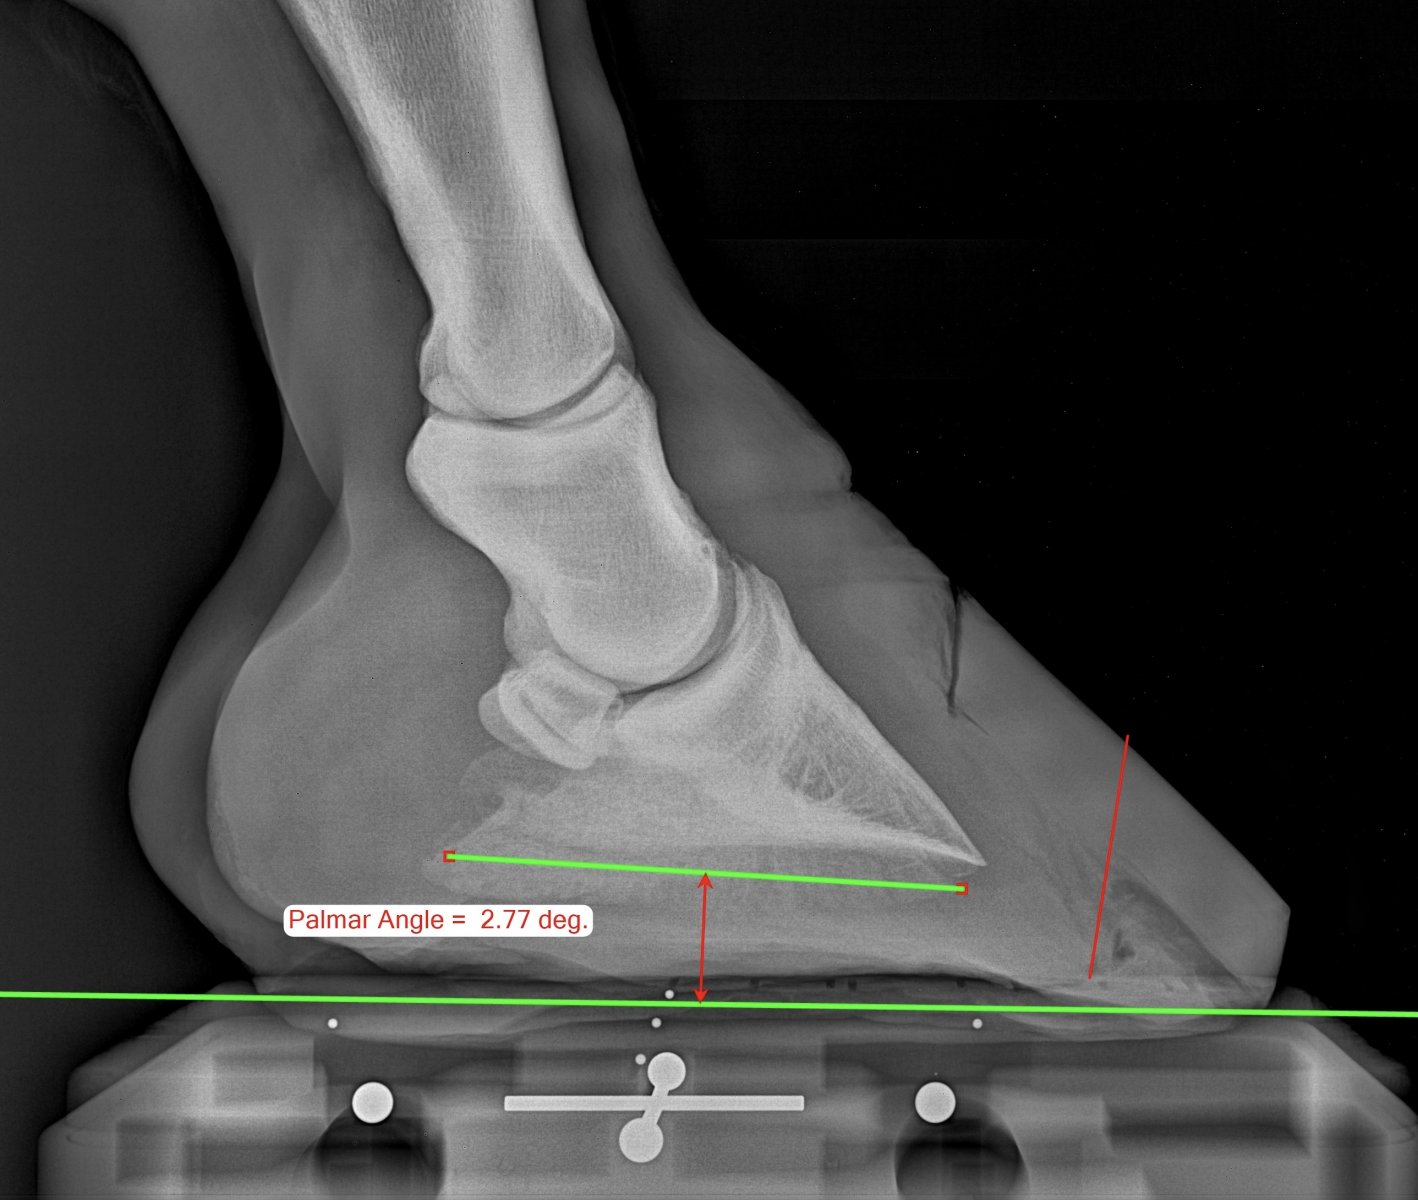

18 лет, забрала из максимально херовых рук. Не ходил, ел овёс и пасся

Сейчас мы пытаемся ходить, наблюдаемся у разных врачей, набираем вес(истощенный пипец), даю ему ламинатор(почти закончился, посоветуйте другие подкормки), масло льна, биотех-ц «сбор при ламините», и лактобифадол(если сильно больно ему, колим неуротранк+флуниджект)

+ортопедическая ковка